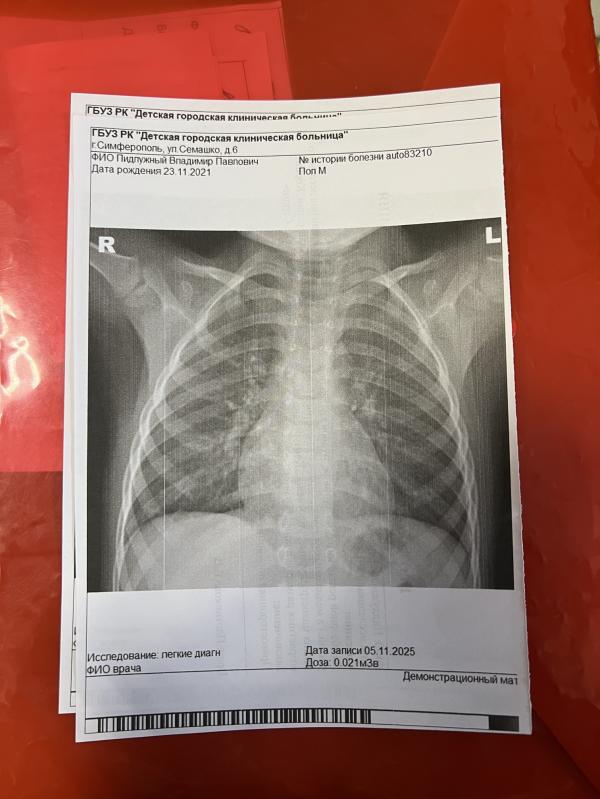

Наша педиатр направила на дневной стационар нас, потому что по дыханию прослушивали не один раз и все спокойно, думали кашель дает нос, из-за затека по задней стенке.. А тут вот отправили снимок сделать, да анализы сдать, я и прифигела от результатов..

Спасибо! В год сталкивались с бронхитом обструктивным и вот сейчас - пневмония. Поэтому даже не ожидала что так может быть🙈

Спасибо! Пока амбулаторно, ну и плюс в дневной стационар на процедуры будем приезжать. Выдали сегодня там антибиотик, сделали от кашля назначение, сегодня оак и на глюкозу сдали, завтра еще на биохимию с вены брать будут. Через 3 дня смотрят динамику. Кстати была приятно удивлена, что выдали лекарство. Пускай и один антибиотик, но все же.